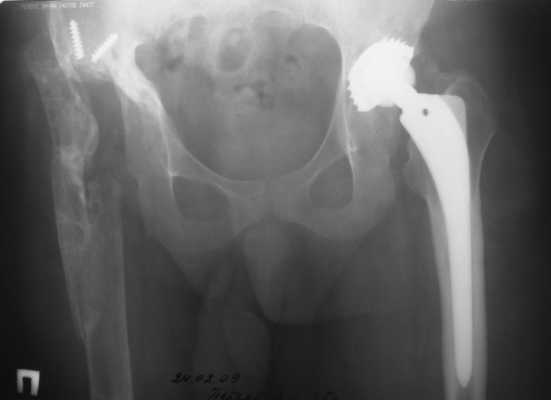

2003 г. нестабильность тазового компонента (рис. 2) - протез удален.

2005 г. при падении с высоты - перелом бедра в верхней трети, наложение АВФ . 3 года пациент ходил с аппаратом(рис. 3).